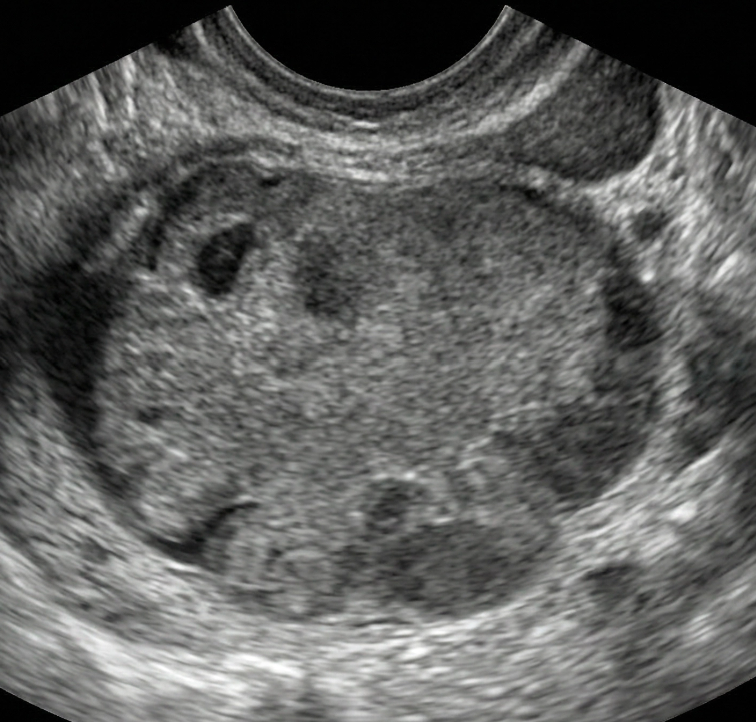

As regras simples do IOTA são um sistema de classificação baseado em características ultrassonográficas específicas que ajudam a distinguir massas anexiais benignas de malignas.

Classificação Benigna: Quando apenas regras benignas estão presentes (uma ou mais).

Classificação Maligna: Quando apenas regras malignas estão presentes (uma ou mais).

Classificação Indeterminada: Quando nenhuma regra está presente, ou quando há presença simultânea de regras benignas e malignas.